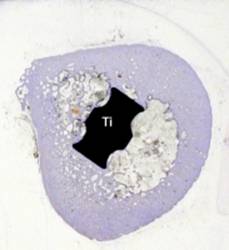

Der SL-PLUS® Schaft besteht aus einer geschmiedeten Titan-Aluminium-Niobium-Legierung (Ti6Al7Nb). Die Pfanne ist aus Reintitan gefertigt. Titan wird vom Körper akzeptiert und vom körpereigenen Knochengewebe gut eingebaut (osseointegriert). Man spricht deshalb von biologischer Verankerung (Literaturnachweis: Zweymüller K., Lintner F., Semlitsch M.: Biologic fixation of a press-fit titanium hip joint endoprosthesis. Clinical Orthopaedics and Related Research 235: 195-206, 1988) (Abb. 19 - 21). Allergien gegen Titan sind nicht bekannt. Demgegenüber stellt die Verwendung von Knochenzementen (Acrylharzen) eine rein mechanische Verankerung dar und führt zur massiven Beeinträchtigung der Blutgefäßversorgung des Markraumes des Oberschenkelknochens.

Abb. 19

Querschnitt durch einen Titanschaft (Ti) und den umgebenden Oberschenkelknochen. Dieser umwächst das Implantat in direktem Kontakt: das Titan wird vom Knochen osseointegriert (mehrere Jahre postoperativ)